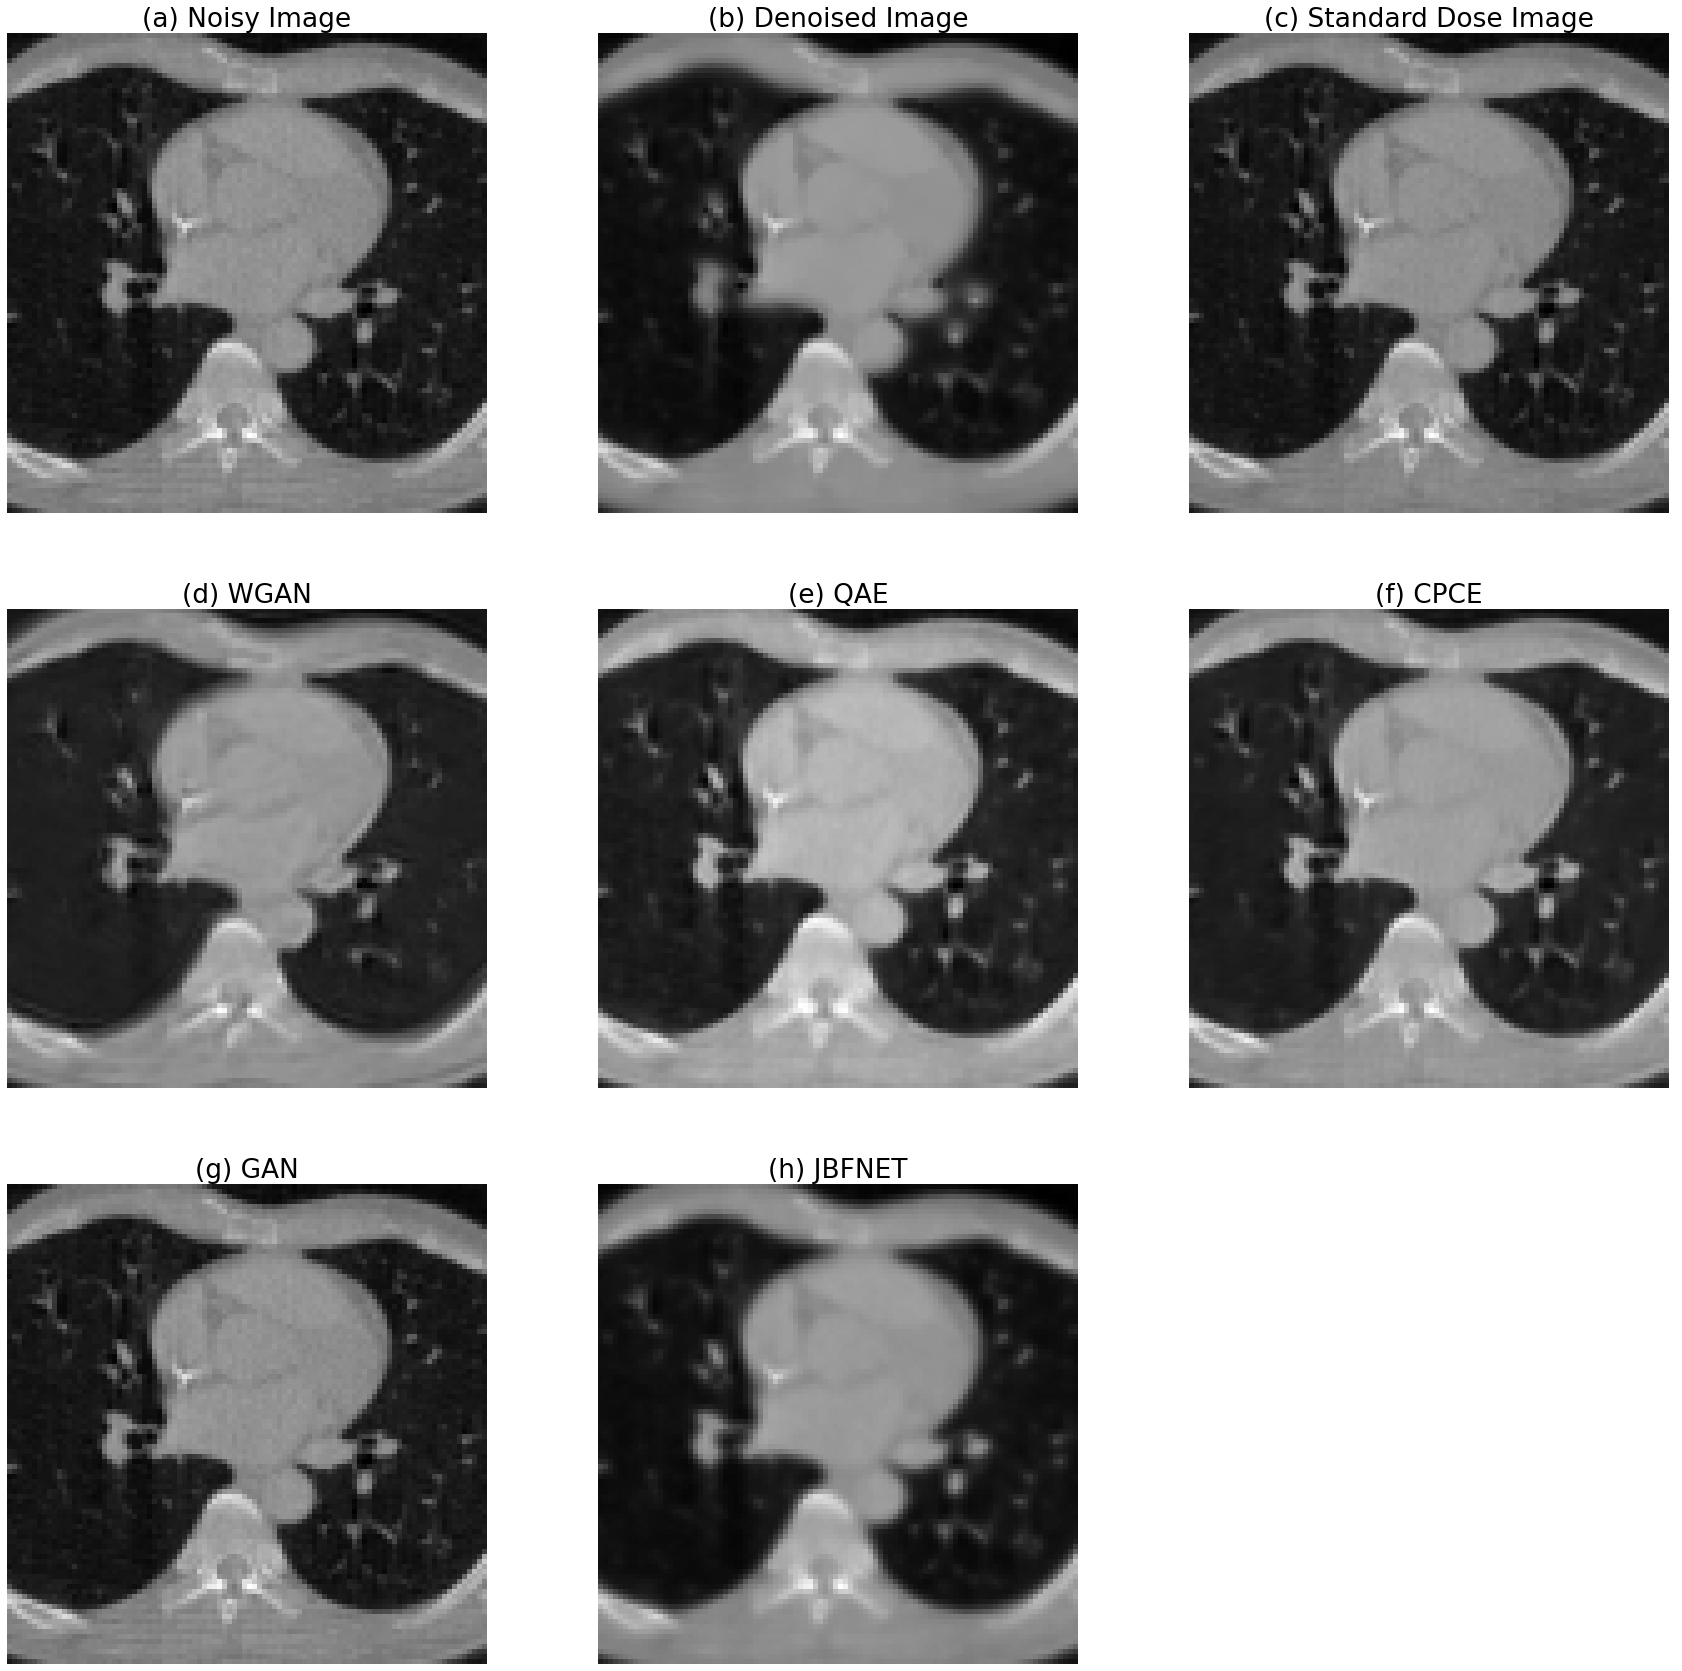

Figure 4: Denoising results compared to other methods

Figure 4 shows the results from our approach and other methods pretrained with other CT images. the results can be compared to others.

We can find that JBFNet and this approach were robust to some points. It is because the others are basically based on image translation neural network models. However our approach and JBFNet learn parameters for filtering. therefore, it doesn’t get effected so much on the difference of geometries or image range, etc. Therefore, those approaches can have comparably robust results.

There is a proof for the image domain range issue in Figure 4. after matching the image domain range to how much the models are pre-trained with training dataset with. the images quality got better notably. it can be one of future benefits of using this approach. this method can be robust to any range of HUs so that it can be applied to general problems. before matching the domain, the metric values including PSNR and SSIM of the GAN-based models don’t look good, which means GAN-based models are over-sensitive to the image domain range and geometries of training data. and on the other hand, QAE, JBFNet, this approach are robust from image domain range issue.

In Figure 5, we can compare specific areas of results. There is a disadvantage of models based on domain filtering including our works and JBFNET. the image in the middle is clearer than others but the outside of images are a bit blurry.